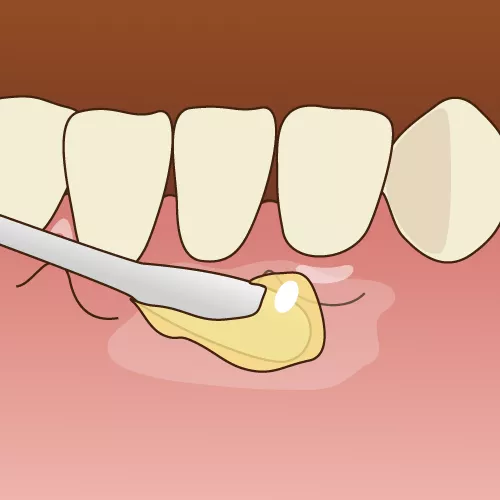

① 表面麻酔を塗る

歯ぐきの注射を打つポイントに麻酔を塗ることで、針が刺さる痛みを軽減します。